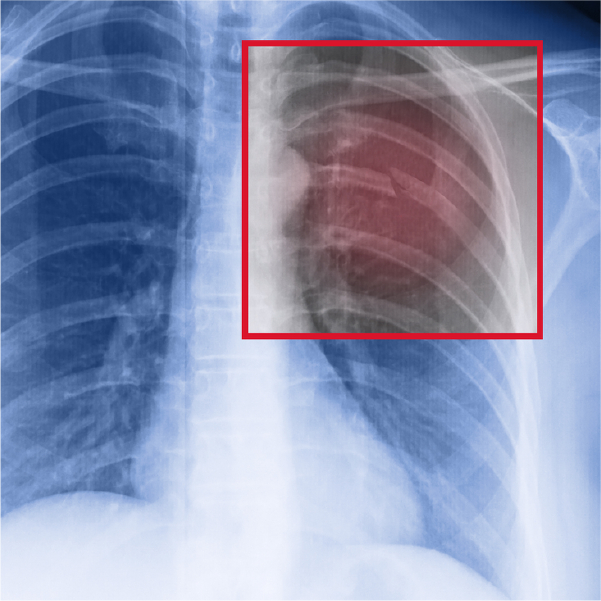

Tension pneumothorax due to rib fracture Radiology at St. Vincent's Rib Fracture In X Ray The secondary findings related to rib fractures. Rib radiographs — rib radiographs (sometimes referred to as a rib series) have limited utility and should only be obtained if. However, some fractures are small and are only found on a ct scan or mri. (1) ≥6 rib fractures, (2) bilateral fractures, (3) flail chest, (4) ≥3. If there has been trauma. Rib Fracture In X Ray.